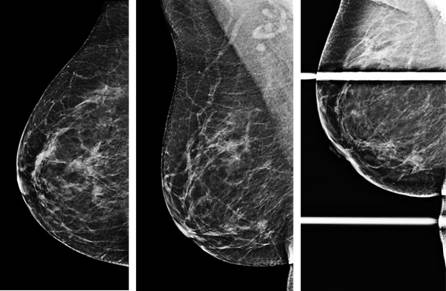

Se contó con 32 reportes de ultrasonido y mastografía, lo que corresponde al 55.17% de las pacientes con diagnóstico de cáncer de mama triple negativo. Los principales hallazgos fueron masa irregular (85%), bordes lobulados (65%), márgenes espiculados (15%), asimetría focal (25%), distorsión de la arquitectura (15%), microcalcificaciones (15%) y sin alteraciones (5%). En la Figura 2 podemos observar un ejemplo de una mastografía con una lesión ocupante triple negativo Figuras 2 y 3. En la Figura 4 podemos observar el hallazgo en un ultrasonido con cáncer ductal infiltrante poco diferenciado, característico del cáncer de mama triple negativo.

Figura 3: Femenino de 60 años, proyecciones mastográficas CC y MLO con una lesión irregular de contornos espiculados en el cuadrante inferior interno de la mama derecha, Ca ductal infiltrante moderadamente diferenciado. Inmunohistoquímica: RE (-), RP (-), HERB2 (-), Ki67 (60%), CD-34 (10), P-53 (100%).